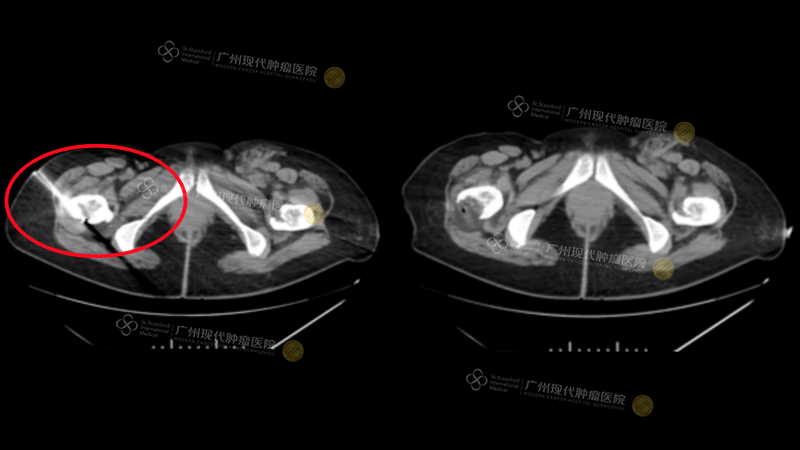

Through a series of typical cases, Professor Wang vividly illustrated the clinical application value of these minimally invasive techniques. One case involved a breast cancer patient with bone metastases whose pre-treatment pain score (NRS) was as high as 10. Even with high doses of conventional painkillers, the relief was insufficient. After multidisciplinary team (MDT) discussion, a CT-guided cryotherapy was performed, resulting in significant pain relief and a marked improvement in the patient’s quality of life.

Another case involved a breast cancer patient with post-operative recurrence and chest wall and bone metastases. This patient also faced unsatisfactory pain relief with conventional medications (NRS 8). After undergoing radioactive seed implantation, the patient’s pain was effectively controlled, and both quality of life and functional status (Karnofsky Score) improved.